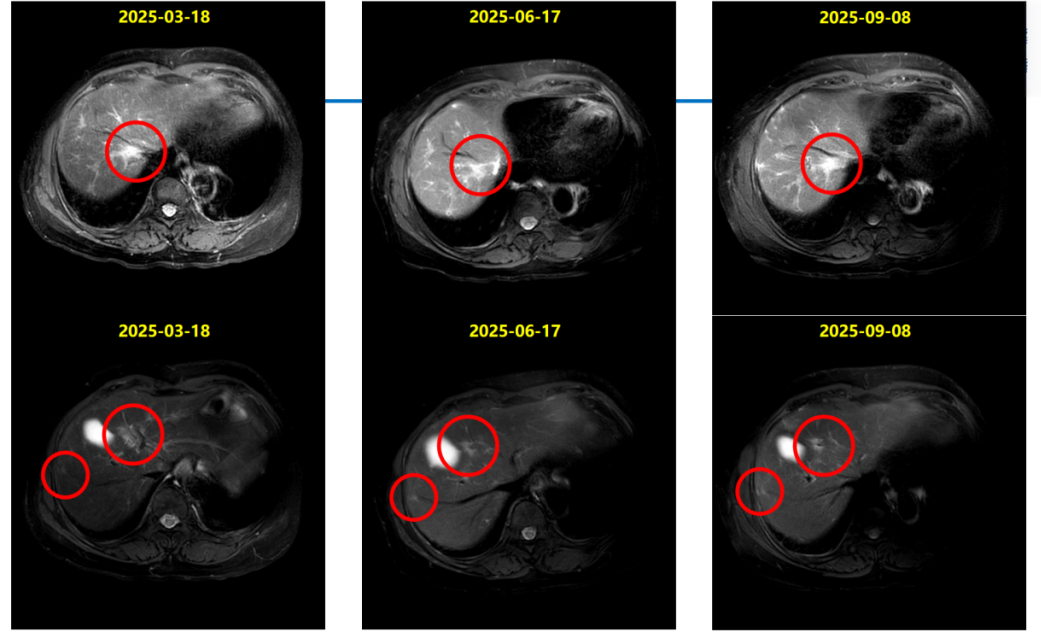

2024-06-18上腹部MR:乳腺癌肝转移化疗后复查,对照2024.03.21MR:肝多发转移瘤,较前增多、增大。部分胸椎异常信号,考虑转移,较前相仿。

DB-04研究结果显示,在总人群中,T-DXd组的中位总生存期较化疗组显著延长;基于该研究结果,国内外多项权威指南已一致推荐T-DXd作为HER2低表达晚期乳腺癌的标准治疗方案,尤其适用于既往接受过治疗的患者。基于DB-04的研究数据、国内外指南推荐及其可及性,患者于2024-07-08至2025-02-25予11周期“德曲妥珠单抗300mg,q3w”治疗,2周期后PR。

患者于2010年5月行左侧乳腺癌根治术,术后接受辅助化疗及他莫昔芬内分泌治疗,疾病稳定长达10年。2020年出现胸壁及淋巴结转移,后历经多线治疗,包括来曲唑治疗、化疗及CDK4/6抑制剂维持,疾病仍持续进展。基于DB-04研究的优异数据,患者于2024年7月启动二线T-DXd单药治疗,2周期后即达PR,显示出T-DXd在HR+/HER2低表达人群中的高效性。

同时在T-DXd治疗过程中,患者于第11周期后出现右肺下叶炎症,经影像学评估确诊为1级间质性肺病。我们立即启动大剂量甲泼尼龙治疗,后逐步减量,ILD在22天内明显缓解,45天内基本消失。在确保ILD完全控制后,我们于2025年5月再启动T-DXd治疗,患者持续获益,影像学评估持续PR。该病例充分体现了在T-DXd使用过程中ILD这一关键不良反应的可管理性。通过早期识别、及时干预、规范减量和再挑战,患者不仅安全度过风险期,还继续从T-DXd治疗中持续获益。

本病例中的患者为HR+/HER2低表达晚期乳腺癌,既往经内分泌治疗、化疗及CDK4/6抑制剂治疗后出现疾病进展,符合DB-04研究患者的入组条件且2024年T-DXd已经在我国获批HER2低表达领域的适应症,并实现药物可及。本例患者在接受T-DXd治疗2周期后即达PR,目前PFS已超过20个月且仍在持续接受治疗,这一案例进一步支持了T-DXd在HER2低表达晚期乳腺癌中的应用。